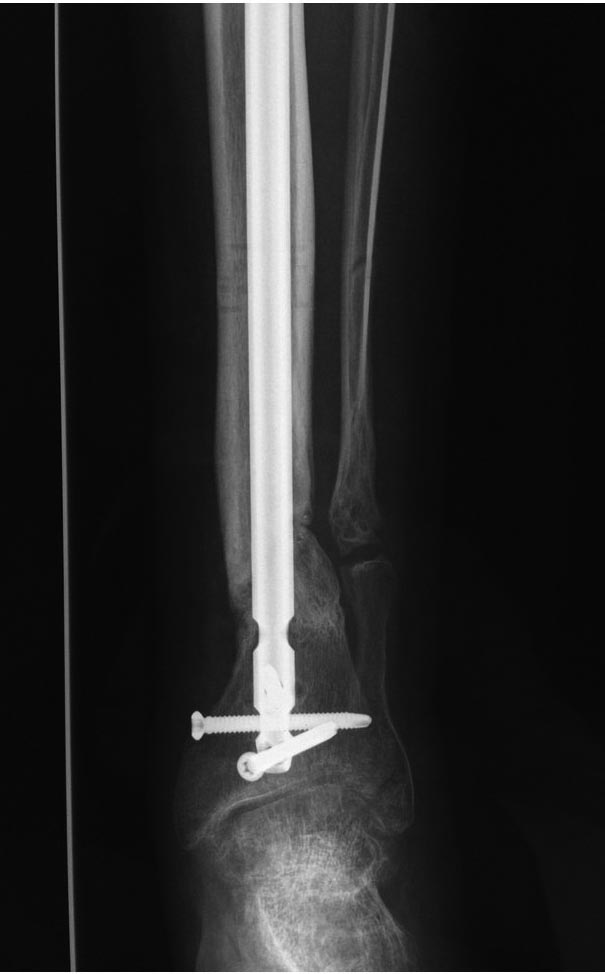

Уважаемые коллеги выразите Ваше мнение по следующему случаю.Молодой человек, 27 лет, находится на лечении с диагнозом: Ложный сустав большеберцовой кости в нижней трети, фиксированный интрамедуллярным блокированным стержнем (12.02.2014 г), ложный сустав малоберцовой кости в нижней трети левой голени, посттравматический артроз левого голеностопного сустава 1 стадии. Укорочение левой нижней конечности на 1,0 см. Со слов пациента известно, что в детстве получил перелом большеберцовой кости, лечился консервативно, перелом сросся с деформацией. Травма в июле 2010 г. бытовая-упал на лестнице, получил перелом малоберцовой кости, и перелом большеберцовой кости без смещения. Выполнена операция: Остеотомия большеберцовой кости в нижней трети, интрамедуллярный блокированный остеосинтез большеберцовой кости левой голени. Гладкое течение послеоперационного периода. Перелом большеберцовой кости сросся. Функция конечности восстановилась. В июне 2013 г выполнена операция удаление интрамедуллярного стержня из большеберцовой кости левой голени. Гладкое течение послеоперационного периода. Приступил к занятием физкультурой, бег. В августе 2013 г спрыгнул с автобуса, с чемоданом в руках, появилась резкая боль в левой голени. За медицинской помощью обратился через 7 дней, при обследовании выявлено: Рефрактура большеберцовой кости. Рекомендовано консервативное лечение в гипсовой повязке. В январе 2014 г. установлен диагноз: Ложный сустав большеберцовой кости в нижней трети, малоберцовой кости в нижней трети левой голени. Контрактура сгибательно - разгибательная левого голеностопного сустава. Посттравматический артроз левого голеностопного сустава 1 стадии. Укорочение левой нижней конечности на 1,0 см. В феврале 2014 г выполнил первым этапом: Фиксацию ложного сустава в АНФ с восстановлением осей сегментов. Через семь дней БИОС с рассверливанием. После операции - вальгус голеностопного сустава. Гладкое течение послеоперационного периода. Нагрузка по переносимости боли. Через 6 недель динамизация, через 2 недели стали мигрировать 2 фронтальных винта. Пытался подкрутить, пришлось удалить. Через 6 мес., контроль - линия ложного сустава прослеживается, но имеется периостальная костная мозоль. Не хватает стабильности.Вопрос что делать?Вариант № 1- выполнить реостеосинтез с рассверливанием КМК и на 12 мм диаметра гвоздь (стоит 11 мм)и убрать ротацию стопы руками одномоментно или одномоментно при помощи АНФ во время операции. Вариант № 2 выполнить удаление гвоздя, сделать все то же, что 6 месяцев назад, но с восстановлением анатомических взаимоотношений в голеностопном суставе.Вариант № 3 Двухэтапно, вторым этапом пластина на большеберцовую кость + костная пластика области не сращения.Вариант № 4 удаление гвоздя и лечение в КДА. Вопросы:1. Какой вариант оперативного лечения будет оптимальным в данном случае.2. При двухэтапной методике в дистальном отломке имеется канал от гвоздя, как направить гвоздь к наружному отделу дистального отломка большеберцовой кости. Есть опасения, что гвоздик может пойти по тому же каналу. Использовать поллер спицы или винты – сработают ли? И достаточна ли будет жесткость фиксации дистального отломка большеберцовой кости на гвоздике при 3 – 4 винтах при реостеосинтезе гвоздем.3. Нужен ли остеосинтез малоберцовой кости в нижней трети, с целью создания латеральной опоры. К сообществу за советом.

Александр Николаевич спасибо за ответ. Три снимка перед внешним видом конечности крайние. На одном из них левая стопа в положении внутренней ротации 15 градусов.

Возможно, не все снимки выставлены, потому что не нашел признаков проведенной динамизации, о которой писали. Верхние винты остались нетронутыми, трудно опознать динамизацию. По поводу применения “cap” на гвозде имеется сомнение, потому что высоко расположенный по верхнему краю гвоздь не позволяет воспроизвести динамизацию. Перед динамизацией надо укорачивать гвоздь или убирать “кап”.